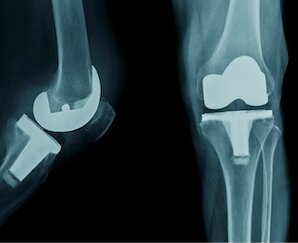

Muscle-Sparing Joint Replacement

Total Knee Replacement (TKR)

Partial Knee Replacement